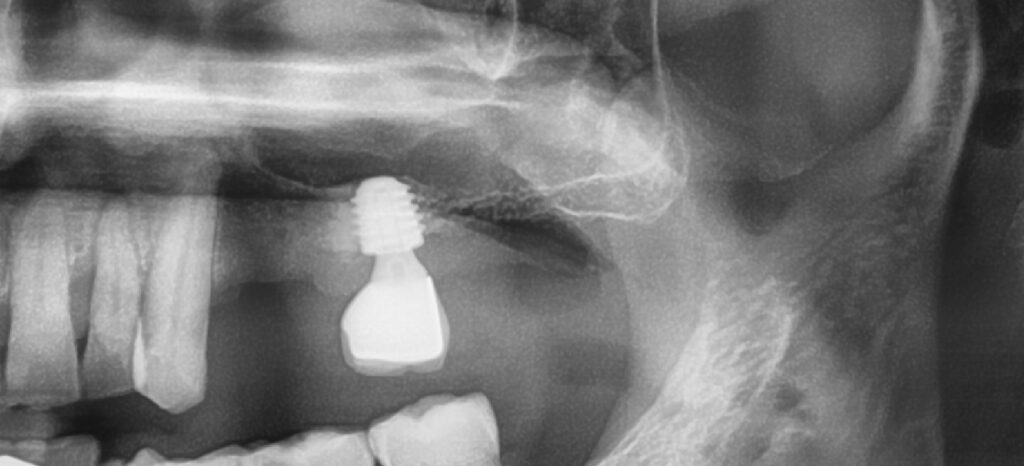

아래 사진을 비교해 보도록 하겠습니다

타치과에서 임플란트 시술을 받고 오신 분인데요

상악동 거상술을 못하는 치과에서

시술을 받다보니

임플란트가 굉장히 짧습니다

이런 임플란트는 문제가 될 소지가 높은데요

짧다고 무조건 나쁜건 아니지만 치아의 크기에 비하여 임플란트 비율이 너무 짧아서 그 기능이 충분하지 못할걸로 보입니다